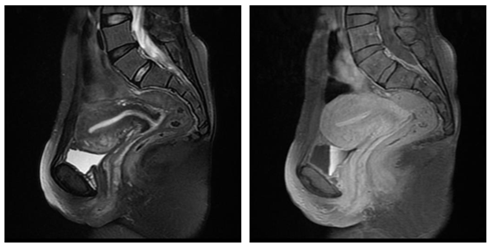

We report a rare case of intramyometrial ectopic pregnancy in a 27year old lady, P3L3 who presented to the emergency department at 8 weeks of gestation with complaints of pelvic pain and haemorrhage not subsiding with medical management. Transvaginal ultrasound revealed an exocentric gestational sac with thick decidua reaction and a “Ring of fire” appearance on color Doppler. Uterine cavity was empty and no adnexal masses visualized. Furthermore, MRI of the pelvis with contrast was done to confirm the location of the ectopic gestation which revealed a well defined T1 isointense T2 hyperintense lesion in the anterior myometrium abutting the junctional zone and showing contrast enhancement. Endometrial stripe was seen separately with an empty uterine cavity. Pouch of Douglas had no free fluid. On diagnostic laparoscopy, an asymmetrically enlarged swollen anterior wall of the uterus was seen. Hysteroscopy was performed concurrently demonstrating an empty uterine cavity. Medical management with methotrexate was initiated following confirmation of the diagnosis. Beta HCG at the time of diagnosis was 9949mIU/ml. She was followed up until the hormone levels returned to baseline and serial scans showed a healed solid collection (Figures 1‒7).

Figure 1 & 2 Coronal T2W spin-echo image and T1+ Contrast image showing well defined hyperintense lesion involving the anterior myometrium showing homogenous contrast enhancement.